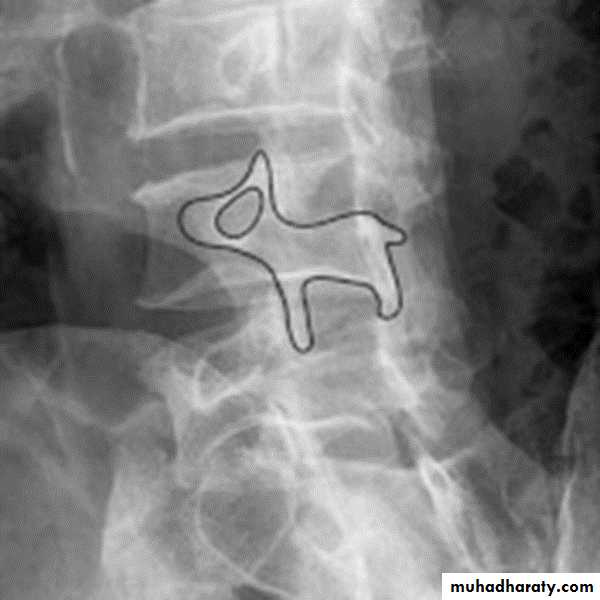

Spondylolysis and spondylolisthesis

Spondylolisthesis: is a term denoting fore ward or backward movement of a vertebra relative to the vertebral segment below, typically due to spondylolysis (pars interarticularis defects) .Spondylolysis: Spondylolysis is a defect in the pars interarticularis of the neural arch, the portion of the neural arch that connects the superior and inferior articular facet in which cause defect in the neck of scotty dog .

scotty dog sign refers to the normal appearance of the lumbar spine when seen on oblique radiographic projection. On oblique views, the posterior elements of vertebra form the figure of a Scotty dog with:

the transverse process being the nose

the pedicle forming the eye

the inferior articular facet being the front leg

the superior articular facet representing the ear

the pars interarticularis (the portion of the lamina that lies between the facets) equivalent to the neck of the dog.